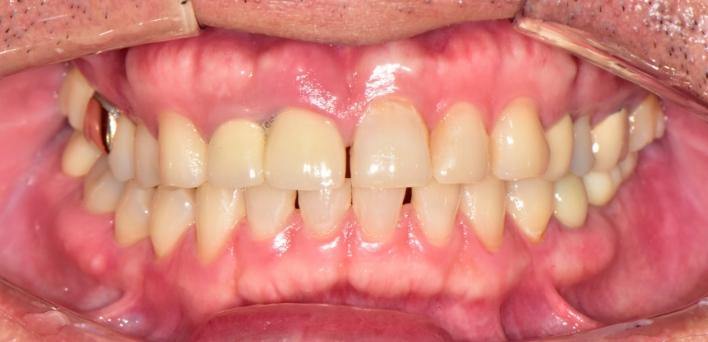

임플란트 : 손 ** 님 (50대)

치아가 있다는게, 아직도 정말 꿈만 같아요.

Before Before

2020.02.30

After After

※ 더서울치과의원은 의료법을 준수하며 위 케이스는 실제 환자의 동의를 얻은 사례로 치료 전, 후가 동일한 환경에서 촬영되었습니다.

환자 케이스에 따라 부작용이 발생할 수 있습니다. 이 부분은 의료진의 충분한 상담과 체크를 통해 예방하고 줄일 수 있습니다.

[임플란트 부작용] 수술 후 관리가 소홀할 경우 출혈, 주위염 등의 부작용이 발생할 수 있어 구강 위생을 철저히 유지하고, 정기적인 검진을 통해 상태를 점검하는 것이 중요합니다.

환자 특징

환자 특징01무치악 상태

환자 특징02수년간 무치악으로 지내심

임플란트가 불가능할것이라

생각하고 내원

위, 아래 6개씩 식립

디지털 풀아치 임플란트